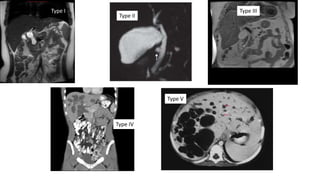

Todani’s classification of choledochal cyst

Types

• I a- dilation of extrahepatic bile duct (entire)

• Ib- dilation of of extrahepatic bile duct (focal)

• Ic- dilation of CBD portion of extrahepatic bile duct

• II- diverticulum of the CBD

• III- cystic dilation of the distal intraduodenal CBD

• IVa-multiple cysts intrahepatically & extrahepatically

• IVb- multiple cysts extrahepatically

• V- single or multiple intrahepatic cysts without extrahepatic

duct dilation.

Type IV

Type V

Occurrence

Type I – 61 %

Type II – less common

Type III – less common

Type IV - 28.5 %

Type V – 4.6%.

Type I

Type II

& III